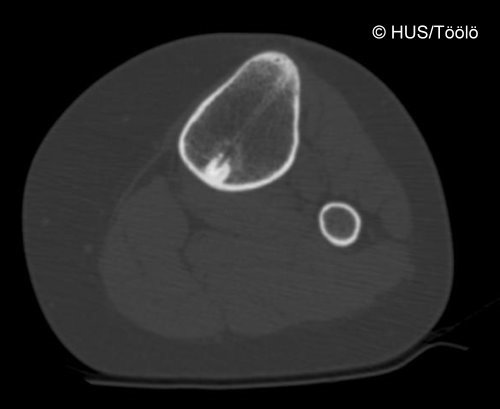

Treated Osteoid Osteoma

Treated osteoid osteoma. Osteoid osteoma after treatment

Picture: Aarne Kivioja / HUCH/Töölö Hospital